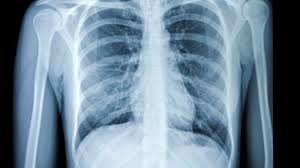

Pneumonia Vs Lung Cancer Symptoms In Dogs : Pneumonia Management Mar Vista Animal Medical Center / It usually results in mild symptoms, mild or no pneumonia, and it resolves within 5 to 7 days.. Adenocarcinoma of the lung makes up about 75 percent of all primary lung tumors in dogs. Pneumonia in dogs can have different causes: Pneumonia is a condition that affects the respiratory system, including the lungs and airways and interferes with your dog's ability to breathe normally. The dog is not coughing up mucus) although the cough may produce small amounts of phlegm or blood. The cause can be bacteria, a virus, or fungi.

Surprising Lung Cancer Symptoms from img.webmd.com These signs are not specific for bronchitis and can also be seen with many other diseases including heart failure, pneumonia, allergic lung disease and lung cancer. Antibiotics may be prescribed to treat pneumonia. Adenocarcinoma of the lung in dogs. Sometimes, people with pneumonia may have symptoms similar to lung cancer. However, primary lung cancers are being seen more frequently over the last 20 years. However, some dogs only experience weight loss (despite a good appetite) and/or lack of energy. In addition it is quite unlikely that the radiologist would mistake lung cancer for pneumonia. Unlike some other types of cancer, there are some concerning symptoms that arise in the earlier stages of primary lung cancer for dogs that should immediately alert you that something is wrong.

Symptoms of primary and metastatic lung cancer are similar, although dogs with metastatic disease don't cough as much, according to the merck veterinary manual. Fungal pneumonia, also called mycotic pneumonia, refers to a fungal infection of the lungs that results in pneumonia caused by breathing in one of many different fungi spores. This time we will discuss lung cancer in dogs symptoms, their life expectancy, diagnosis using x ray, cancer treatment, and stages of lung cancer in dogs. However, some dogs only experience weight loss (despite a good appetite) and/or lack of energy. Other symptoms include exercise intolerance, lethargy and weight loss. These signs are not specific for bronchitis and can also be seen with many other diseases including heart failure, pneumonia, allergic lung disease and lung cancer. Pneumonia is a condition that affects the respiratory system, including the lungs and airways and interferes with your dog's ability to breathe normally. Your veterinarian may recommend an fna and cytology or a biopsy, to confirm the diagnosis, and determine exactly what kind of lung cancer is present. With treatment dogs typically recover well from pneumonia, however if the condition is left untreated symptoms may become severe and more serious conditions could develop. Lung cancer is a general term that includes all abnormal lung tissue cells that multiply unregulated and form tumors or growths in the lungs.these tumor cells may spread (metastasize) to other parts of the body.; Metastatic cancer to the lungs is much more common than primary lung cancer. Pneumonia is an infection of lung tissue usually caused by viruses, bacteria, fungi, and/or parasites.however, bacteria and viruses cause the majority of pneumonia infections. Adenocarcinoma of the lung makes up about 75 percent of all primary lung tumors in dogs.

Pneumonia is a condition that affects the respiratory system, including the lungs and airways and interferes with your dog's ability to breathe normally. In young dogs, viral infection can predispose the lungs to bacterial invasion, and true pneumonia results. Pneumonia in dogs can have different causes: Some of the pneumonia symptoms overlap with those of the cold, but the condition also has discerning symptoms of its own. Bacterial pneumonia is an inflammation of the lung usually caused by bacterial or viral infection but can be caused by inhalation of an irritant. Pneumonia can be mild and only require a week of treatment before you can. If your dog has a chronic cough, you'll need to rule these out. It is caused by a viral or bacterial infection in the respiratory tract. This time we will discuss lung cancer in dogs symptoms, their life expectancy, diagnosis using x ray, cancer treatment, and stages of lung cancer in dogs. Lung cancer can predispose one to pneumonia but in that case the pneumonia would recur in the same place in your lung each time. This is a malignant neoplasm, with the ability to grow rapidly and metastasize to distant parts of the body, including the organs, lymph nodes, bones, brain and eyes. Dog pneumonia can also result from a neuromuscular disorder, which would cause difficulty with swallowing and issues related. Symptoms of pneumonia in dogs will generally appear in the respiratory system, including the lungs, throat, trachea, windpipe, nose, sinuses, and smaller airways known as bronchi and bronchioles.

Pulmonary Blastomycosis Presenting As Primary Lung Cancer Bmc Infectious Diseases Full Text from media.springernature.com Fungal pneumonia, also called mycotic pneumonia, refers to a fungal infection of the lungs that results in pneumonia caused by breathing in one of many different fungi spores. As these can also be caused by other disease, diagnostics include a full physical exam, blood work, radiographs, and may also require bronchoscopy with. Lung tumors have moderate to high potential for metastasis (spreading). With treatment dogs typically recover well from pneumonia, however if the condition is left untreated symptoms may become severe and more serious conditions could develop. This time we will discuss lung cancer in dogs symptoms, their life expectancy, diagnosis using x ray, cancer treatment, and stages of lung cancer in dogs. So what symptoms might make that more likely? Symptoms of pneumonia in dogs will generally appear in the respiratory system, including the lungs, throat, trachea, windpipe, nose, sinuses, and smaller airways known as bronchi and bronchioles. Pneumonia is a common lung infection.